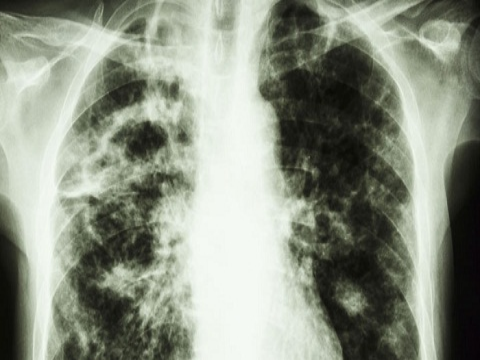

Ngày thế giới phòng chống lao 2015: Những điều ít biết về căn bệnh này